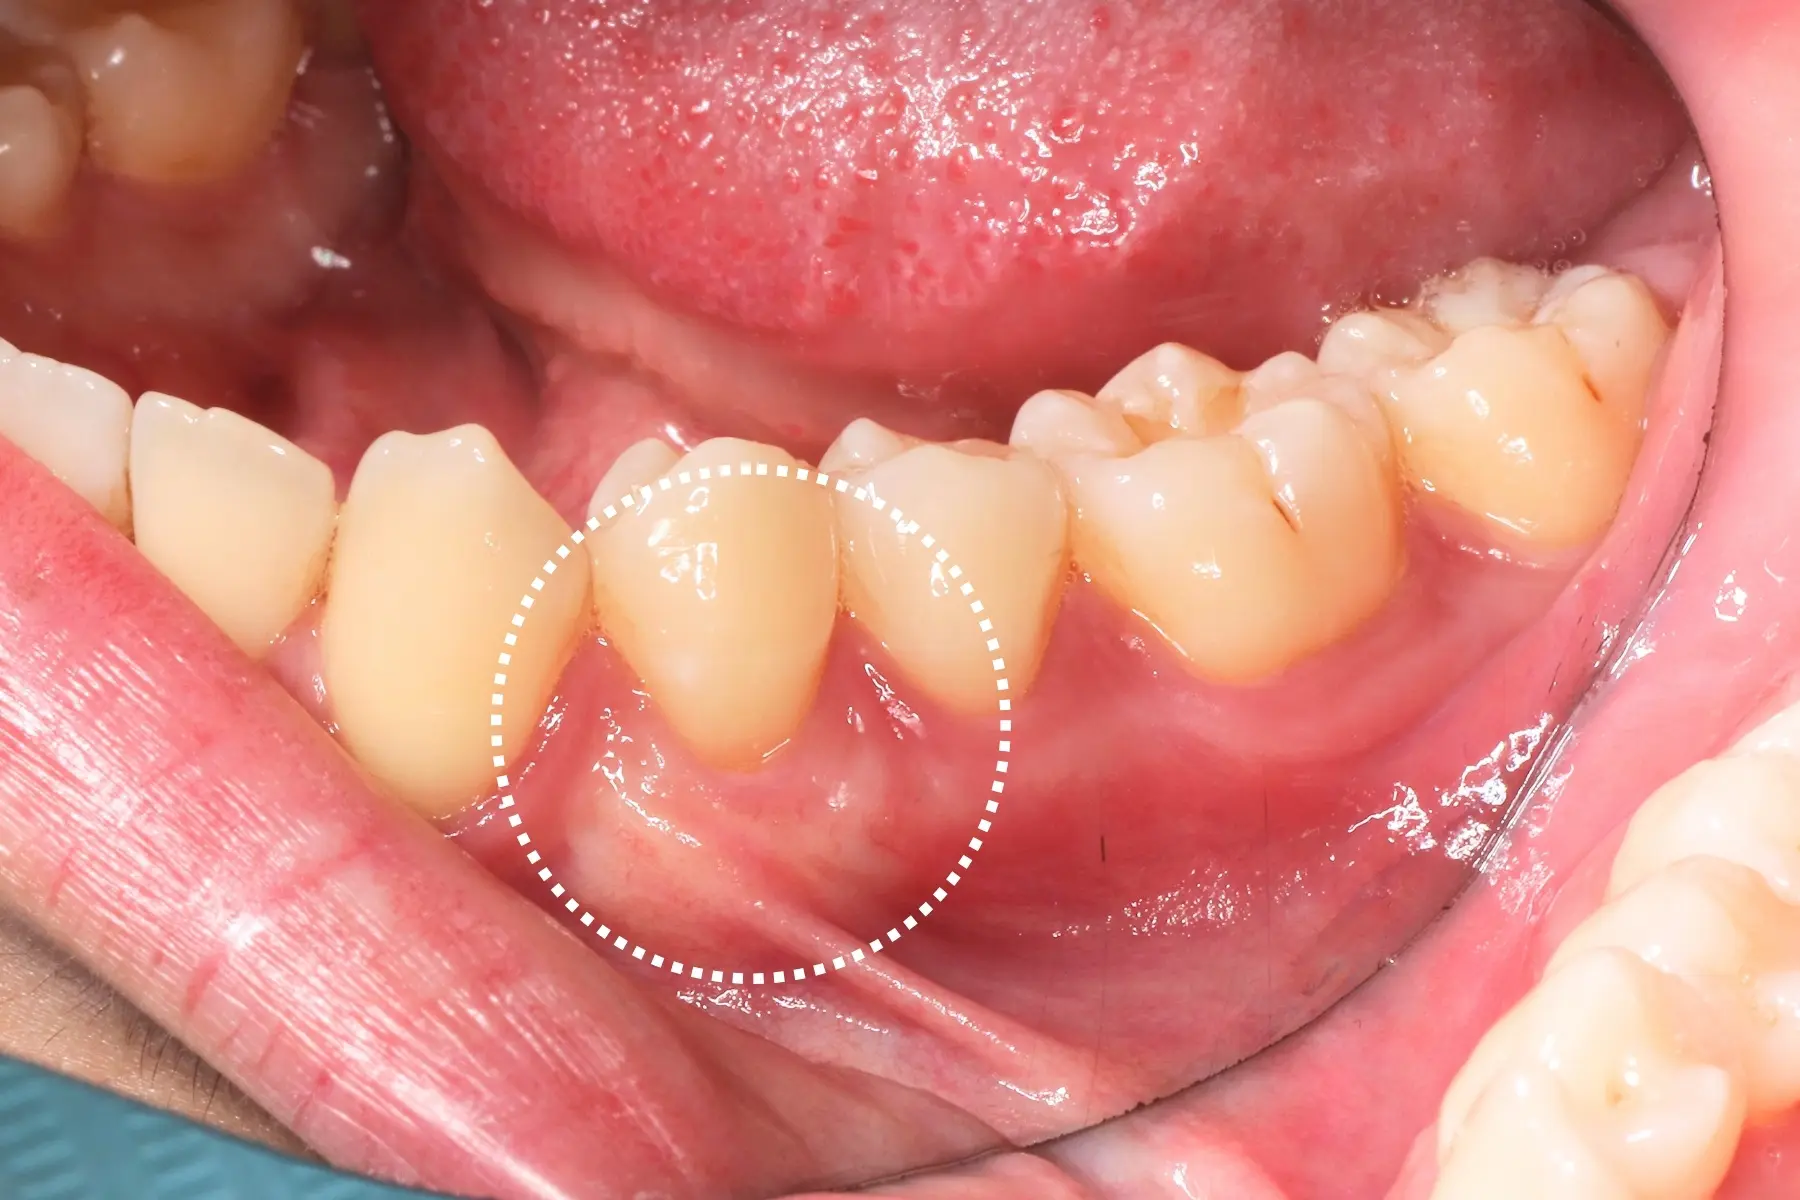

• 術前 42

術後 40

牙周治療

主治醫師

• 鍾國耀

治療時間

三次療程

主訴

右上前牙牙齦反覆腫脹化膿